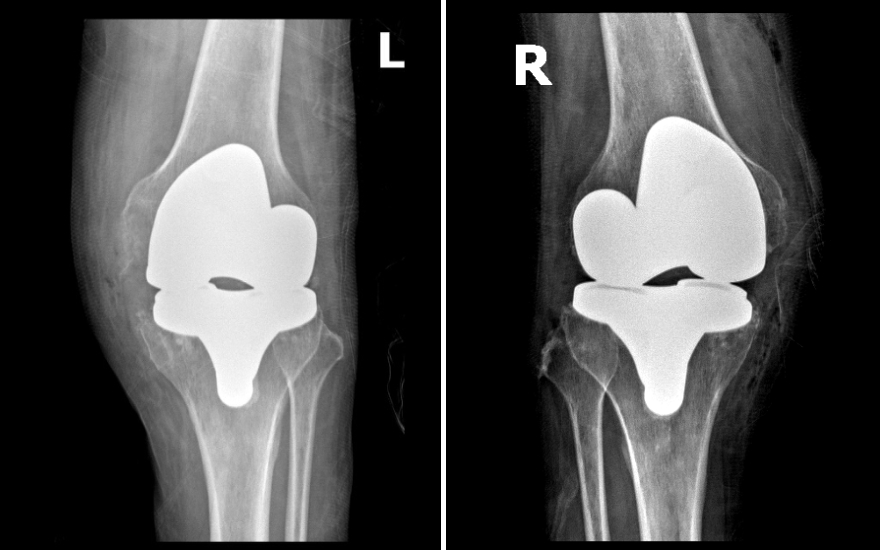

Khớp nhân tạo vừa khít với trục chân của bệnh nhân Giang, cho dáng đi tự nhiên, vững chắc